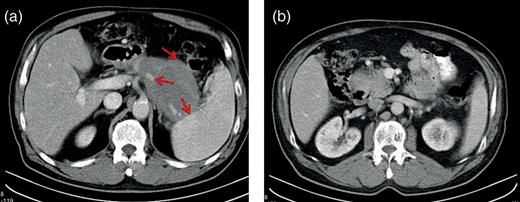

A 60-year-old male is presented with abdominal pain. On CT scan, a 70 × 66 × 48 mm' lesion was identified in the tail of the pancreas. Repeated aspiration demonstrated no malignancy, tumor markers were within the normal range. Control imaging studies showed enlargement of the mass, infiltrative growth, venous compression and appearance of a pathologic lymph node, suggesting a malignant process, therefore we decided surgical exploration (Fig. 1). A solid, malignantly appearing lesion was identified in the body and tail of the pancreas, infiltrating the splenic hilum and transverse colon. A pylorus-preserving total pancreatectomy with splenectomy and extended right hemicolectomy was performed with an uneventful postoperative recovery (Fig. 2).

Preoperative CT scans. (a) The pancreatic mass in the tale of the pancreas, the arrows shows the relationship to the colon, to the spleen and to the splenic artery and (b) the pancreatic mass in the head of the pancreas.